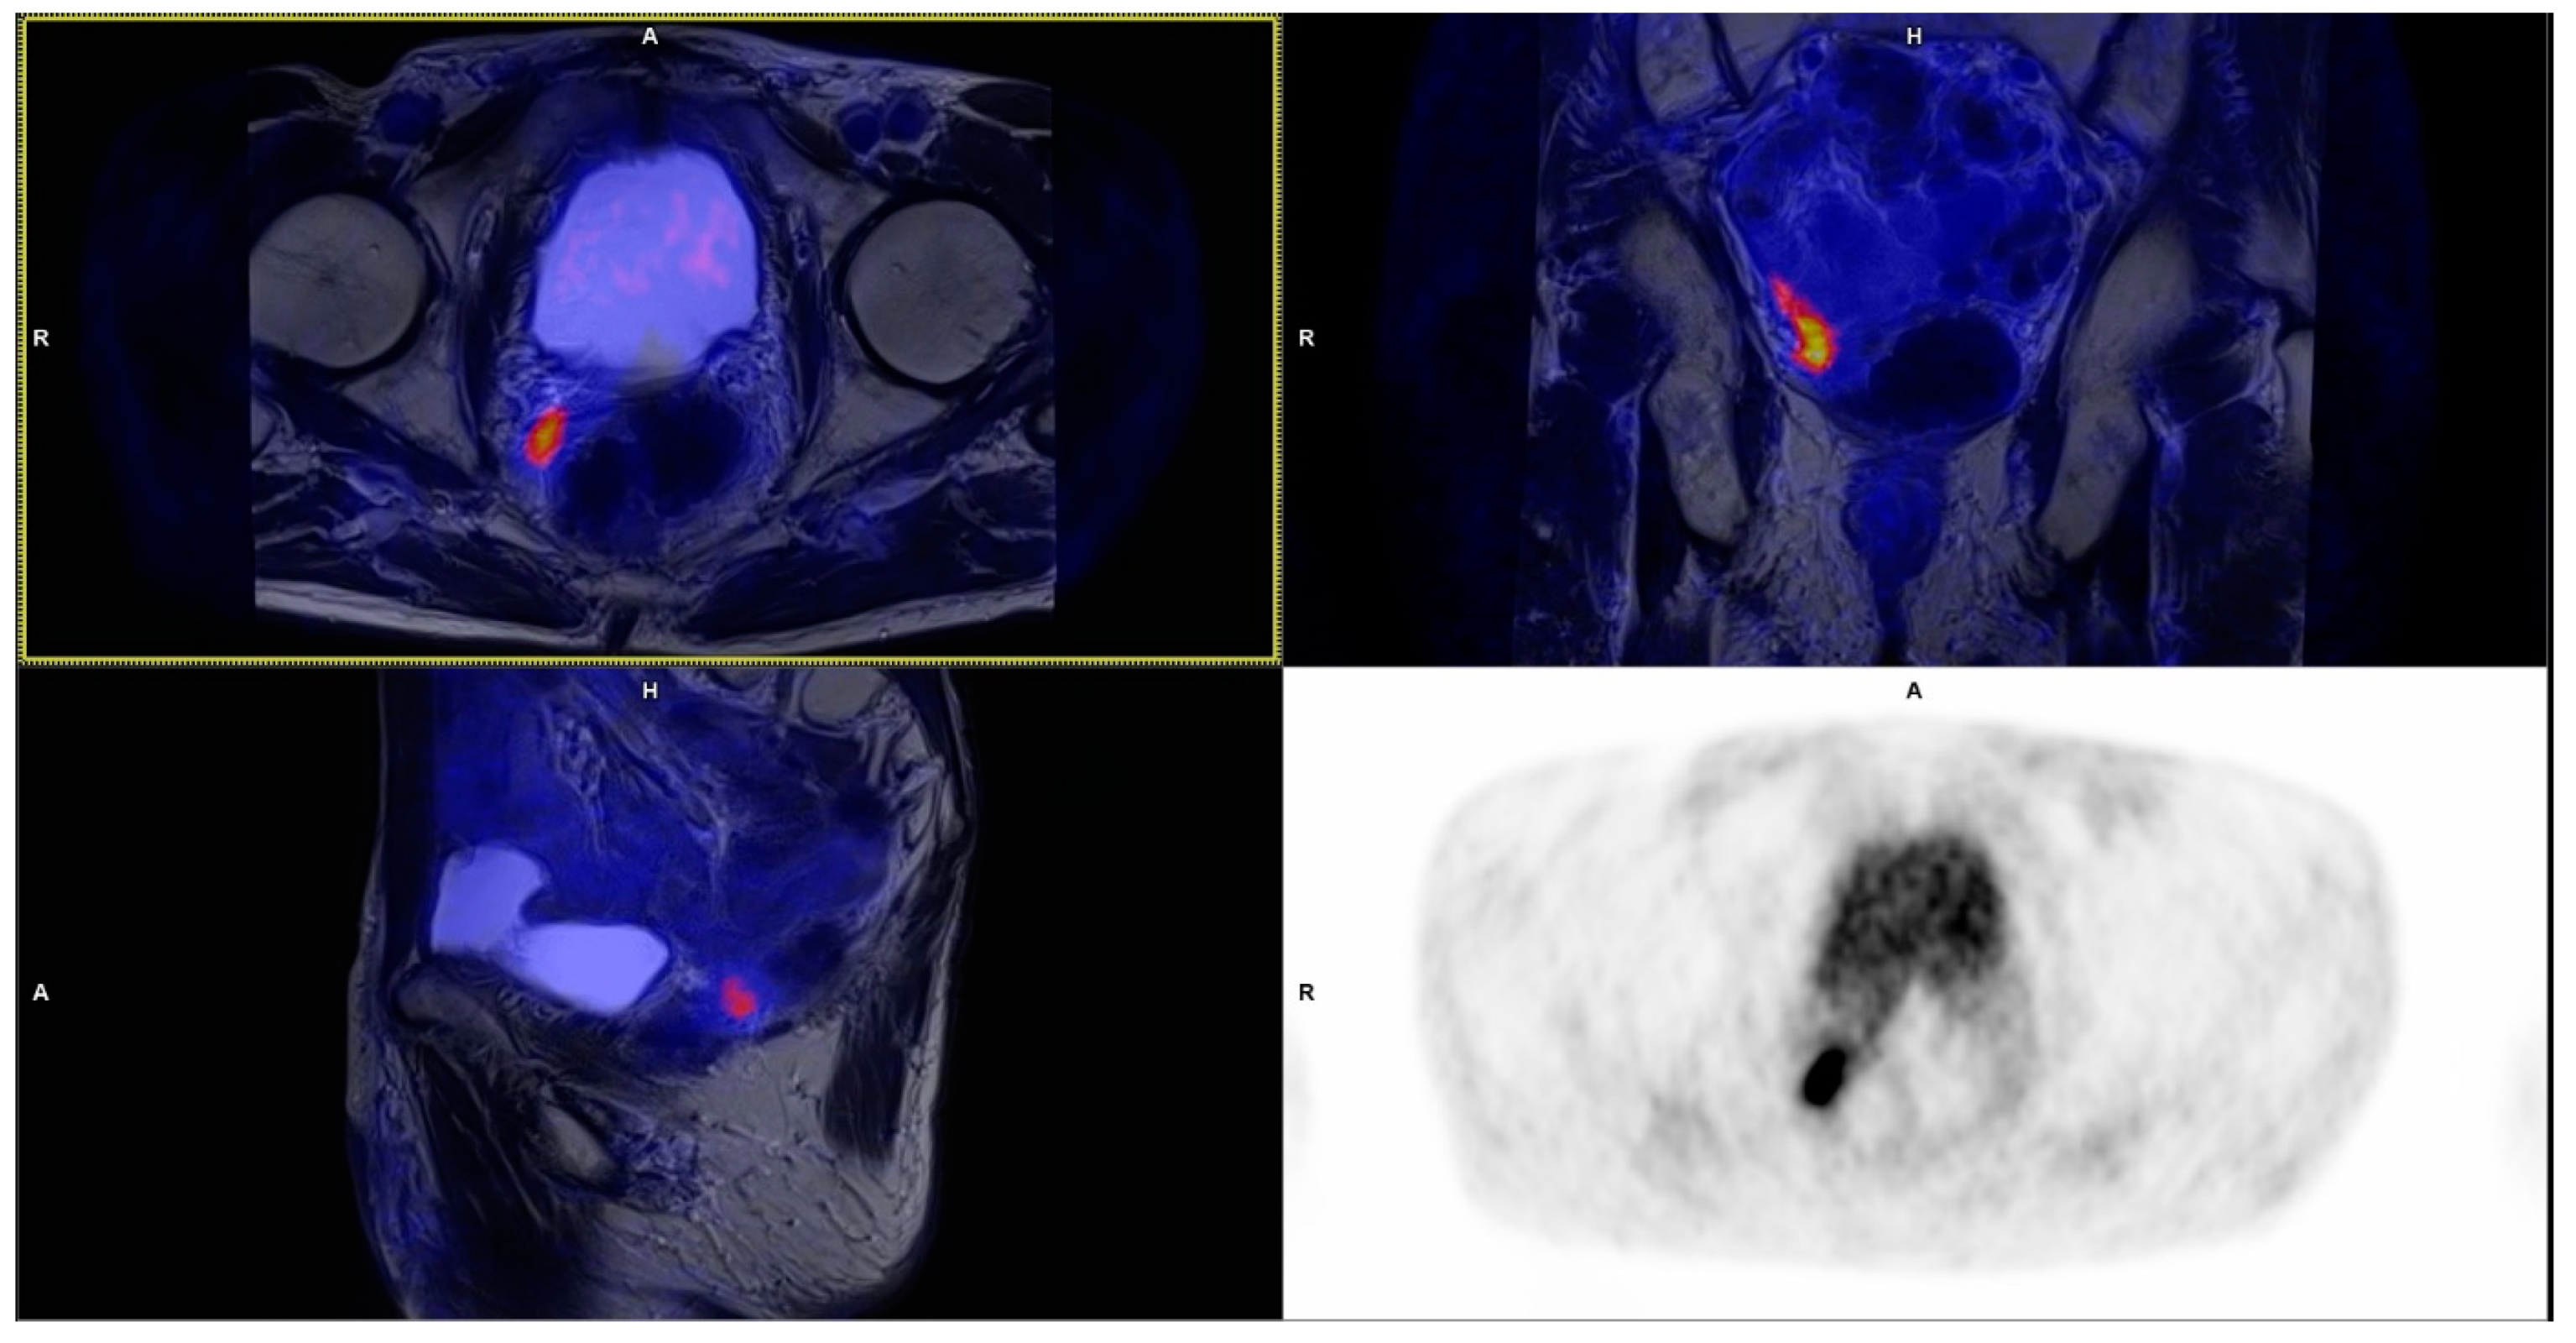

3.1. Local Recurrence

| Prostatic bed | 13 | 6.34 ± 2.53 | 6 × 4 up to 19 × 18 × 25 |